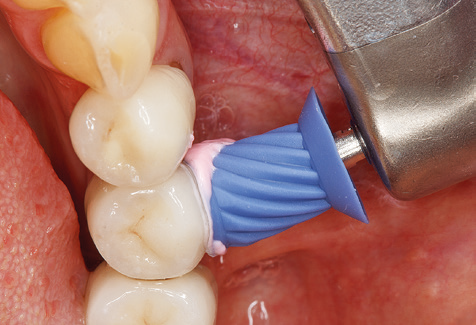

Of course, working tips for the cleaning of implant surfaces are also indispensable for SPT in patients fitted with implants. The implant cleaning attachment on the system used here is characterised by its tapered, hexagonal design. This design allows light, atraumatic penetration of the peri-implant pocket and displays a good cleaning performance (Fig. 7).

Fig. 4: Flexible probes with millimetre markings are recommended for the probing of dental implants (e.g. Colorvue Kit PCV11KIT6, Hu­Friedy). – Fig. 5a and b: A straight working tip (1P, W&H Dentalwerk Bürmoos GmbH) is a suitable instrument for use on all natural teeth. – Fig. 6: Curved working tips (3Pr/3Pl, W&H Dentalwerk Bürmoos GmbH) lend themselves to the processing of difficult-to-reach areas of the tooth and root surfaces (e.g. furcations). – Fig. 7: The tapered, hexagonal implant cleaning tip (1I, W&H Dentalwerk Bürmoos GmbH) permits atraumatic and efficient cleaning of the crown and abutment surfaces. – Fig. 8: Titanium and carbon curettes are suitable instruments for the manual cleaning of the implant surfaces.